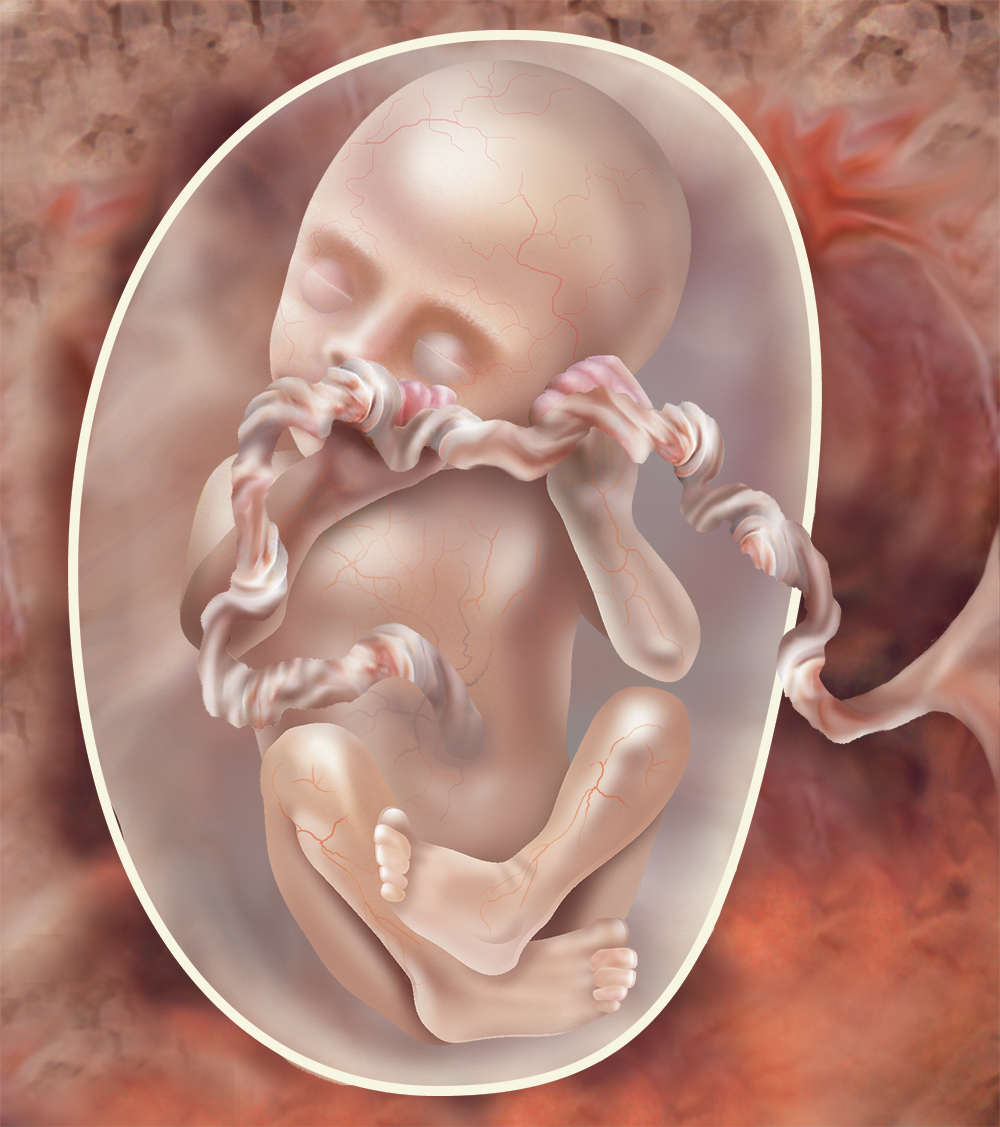

16-17 недель беременности: развитие малыша

Раздел: Житейские мотивы